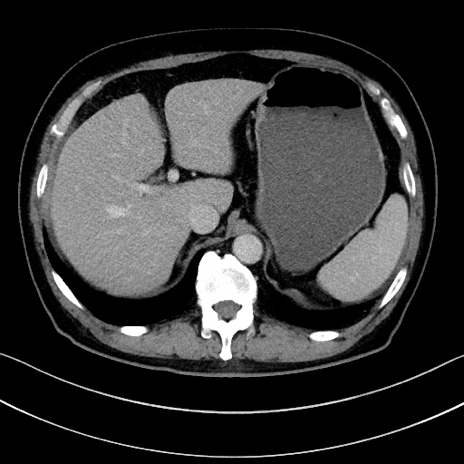

症例15(横断像)

【症例】70歳代男性

【主訴】腹痛

【現病歴】今朝から腹痛あり。全体的に痛い。特に左上の方。排ガスが今日はない。冷や汗が出る。

【既往歴】直腸癌術後

【身体所見】左側腹部〜上腹部に圧痛あり。腹膜刺激症状明らかなではない。軽度反跳痛。左下腹部に術後瘢痕あり。

【データ】WBC 7700、CRP 0.02